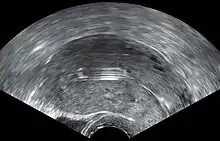

- A "lost coil" occurs when the thread cannot be felt by a woman on routine checking and is not seen on speculum examination.[58] Various thread collector devices or simple forceps may then be used to try to grasp the device through the cervix.[59] In the rare cases when this is unsuccessful, an ultrasound scan may be arranged to check the position of the coil and exclude its perforation through into the abdominal cavity or its unrecognised previous expulsion.